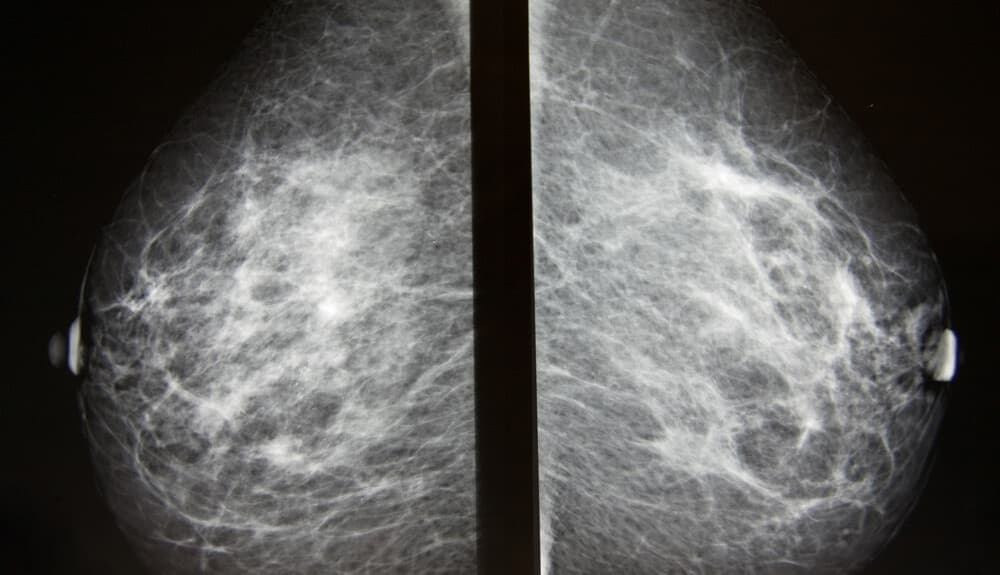

During mammography, X-ray images of the breasts are taken. These can then be used for breast cancer screening or for diagnostic purposes, for example to investigate certain symptoms or unusual findings detected by another imaging method.

During the exposure, the breast is compressed between two solid surfaces so that the breast tissue spreads out. Then black-and-white images are produced by X-ray, which are displayed on a computer screen and examined for signs of cancer. The image is taken with an X-ray machine specifically designed for mammography. To ensure good image quality and to reduce radiation exposure, each breast is compressed individually with special plastic plates and two-directional X-rays are taken of them. A conventional mammography is basically not painful, but the compression of the breasts can be uncomfortable. A technician will help position your head, arms and torso so that the machine can scan your breasts without obstruction.

As mentioned, mammography produces black-and-white images of the breast tissue. These are digital images displayed on a computer screen for the radiologist to analyze.

The radiologist looks for signs suggestive of cancer and other conditions that may require further tests, follow-up or treatment.